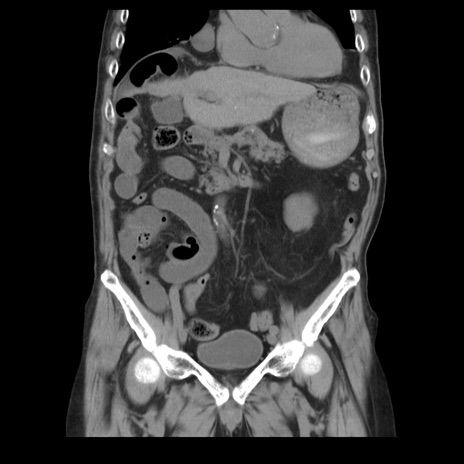

症例21(冠状断像)

【症例】70歳代男性

【主訴】腹痛

【現病歴】肝硬変・肝細胞癌にてかかりつけの方。約9時間前に食後より腹痛出現。症状が徐々に増悪し、嘔吐出現したため来院。

【既往歴】肝硬変、肝細胞癌(RFA、TACE後)

【身体所見】意識清明、表情苦悶様、BT 36℃、BP 129/78mmHg、P 88bpm、SpO2 97%(RA)、右上腹部から心窩部にかけて圧痛あり、反跳痛なし、筋性防御あり。

【データ】WBC 5800、CRP 0.16